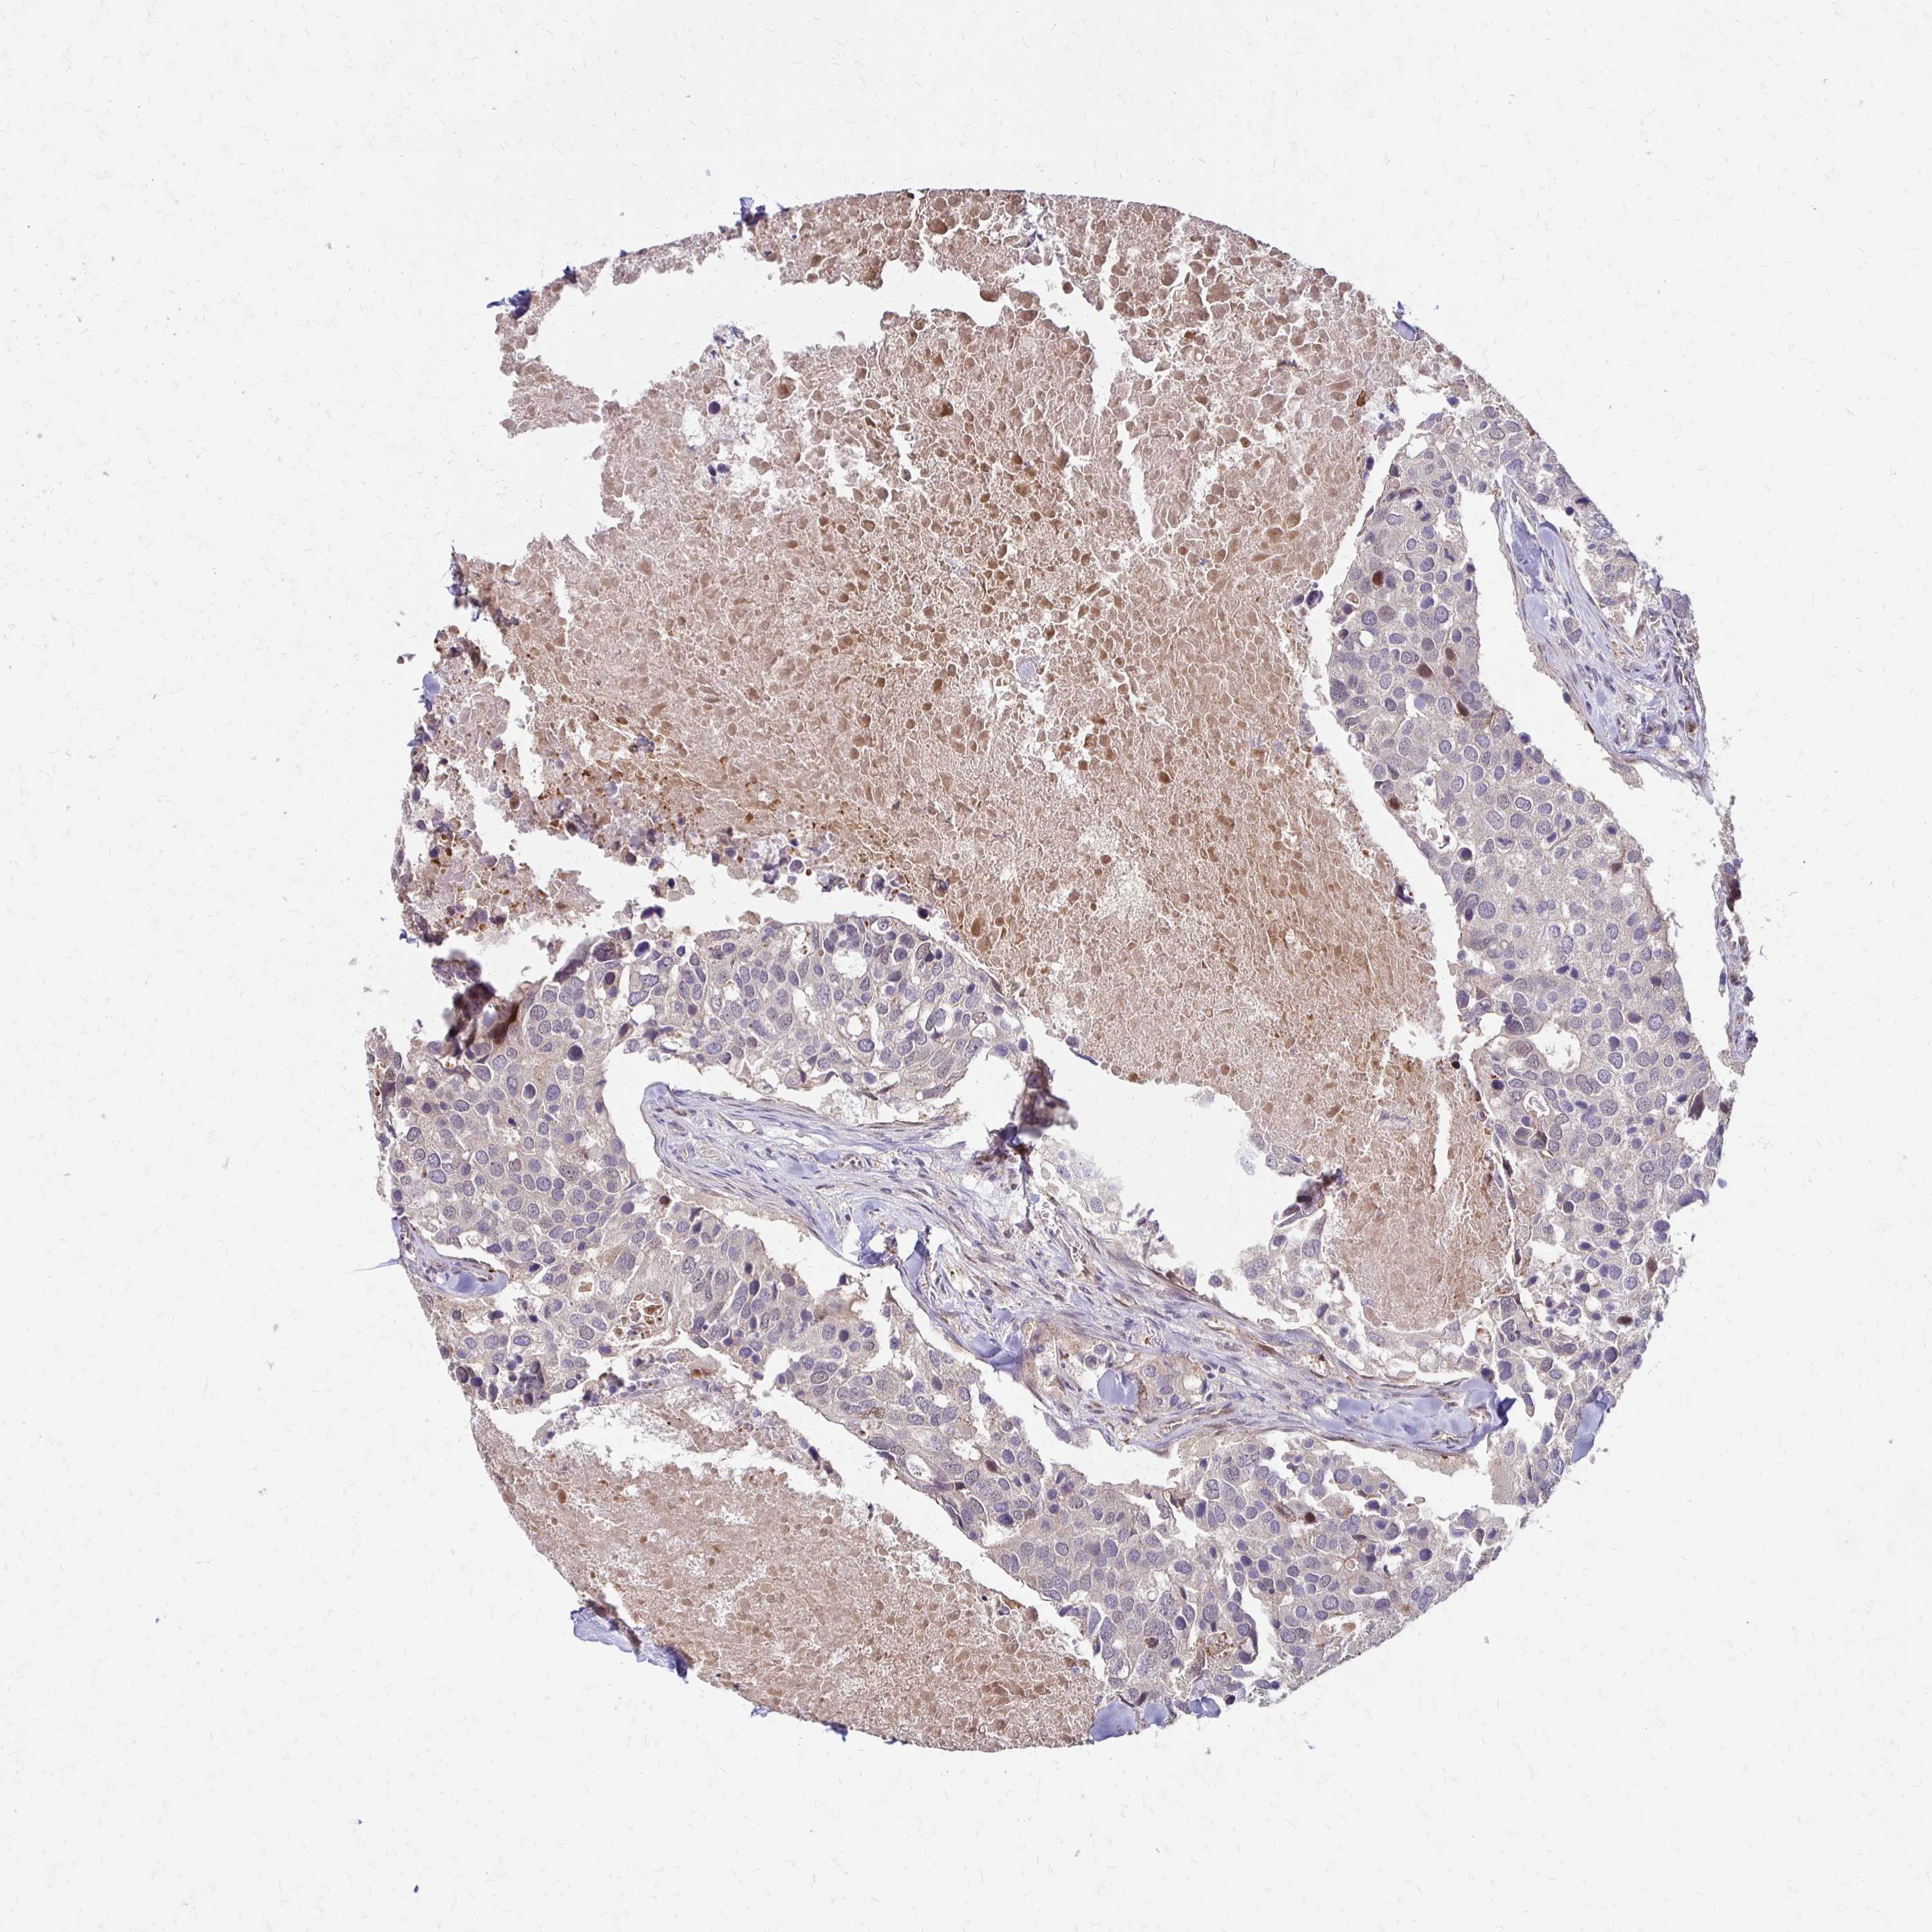

BRCA TCGA BRCA VALIDATION PROTEIN EXPRESSION

ANTIBODIES

AND

VALIDATION